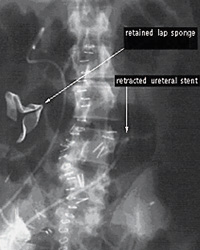

В хирургические материалы будут встраиваться радиочипы, чтобы хирург не смог оставить эти предметы в теле больного

Анекдот про хирурга, забывшего в теле больного скальпель, для многих пациентов вовсе не так смешон, как для их сограждан, не побывавших на операционном столе. По статистике, в одних только США хирурги каждый год забывают в теле пациентов около 1500 предметов. Нередко эти предметы пребывают в теле бессимптомно десятки лет, но иногда небрежность хирурга оборачивается даже гибелью больных.

Но совсем скоро с подобными «подарками пациенту» будет покончено. Это обещают американские ученые и лично координатор проекта доктор Алекс Макарио. В тампоны и другие хирургические материалы будут встраиваться радиочипы, которые будут подавать звуковые сигналы врачу, если тот оставит их в теле больного. Небольшие клинические испытания с участием девяти добровольцев, которым предстояли операции на органах брюшной или тазовой полости, продемонстрировали стопроцентную эффективность новой технологии. Врач при помощи электронного детектора смог в течение нескольких секунд обнаружить и извлечь из тела больного все оставленные там усовершенствованные тампоны.